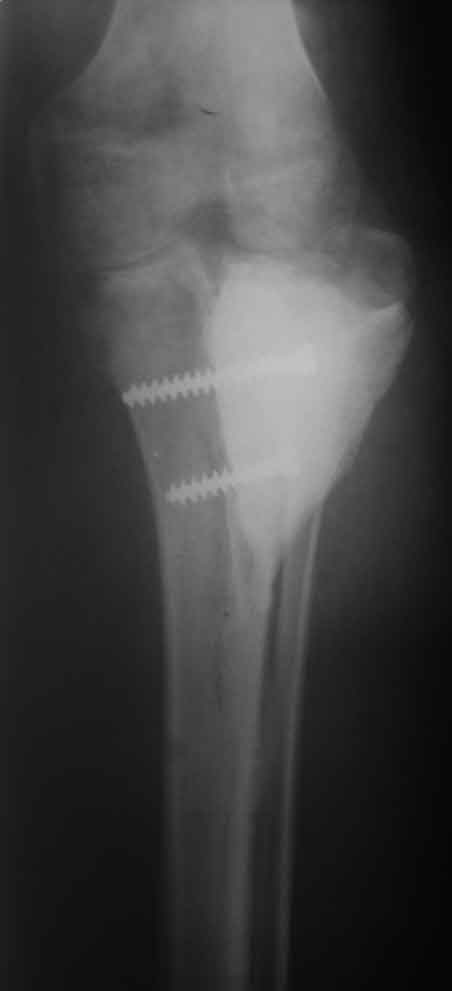

Костный и мягкотканый дефект голени

Рентген, интраоперационные фото и после снятия повязки

Re: Костный и мягкотканый дефект голени

Если получилось(а пока вроде кажется,что -да)поздравляю.Случай очень интересный,я сам не был уверен,что получится с цементом.От суставной то поверхности осталось что?

Из суставной площадки- оставил все и ,к сожалению,она не приросла к основному фрагменту